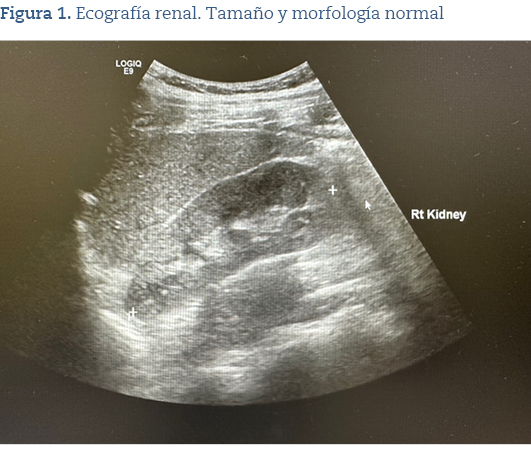

En la ecografía, se objetivó tamaño de ambos riñones normales sin presencia de quistes o nódulos (figura 1), pero en el Doppler (figura 2) se apreciaban flujos disminuidos en ambos riñones.